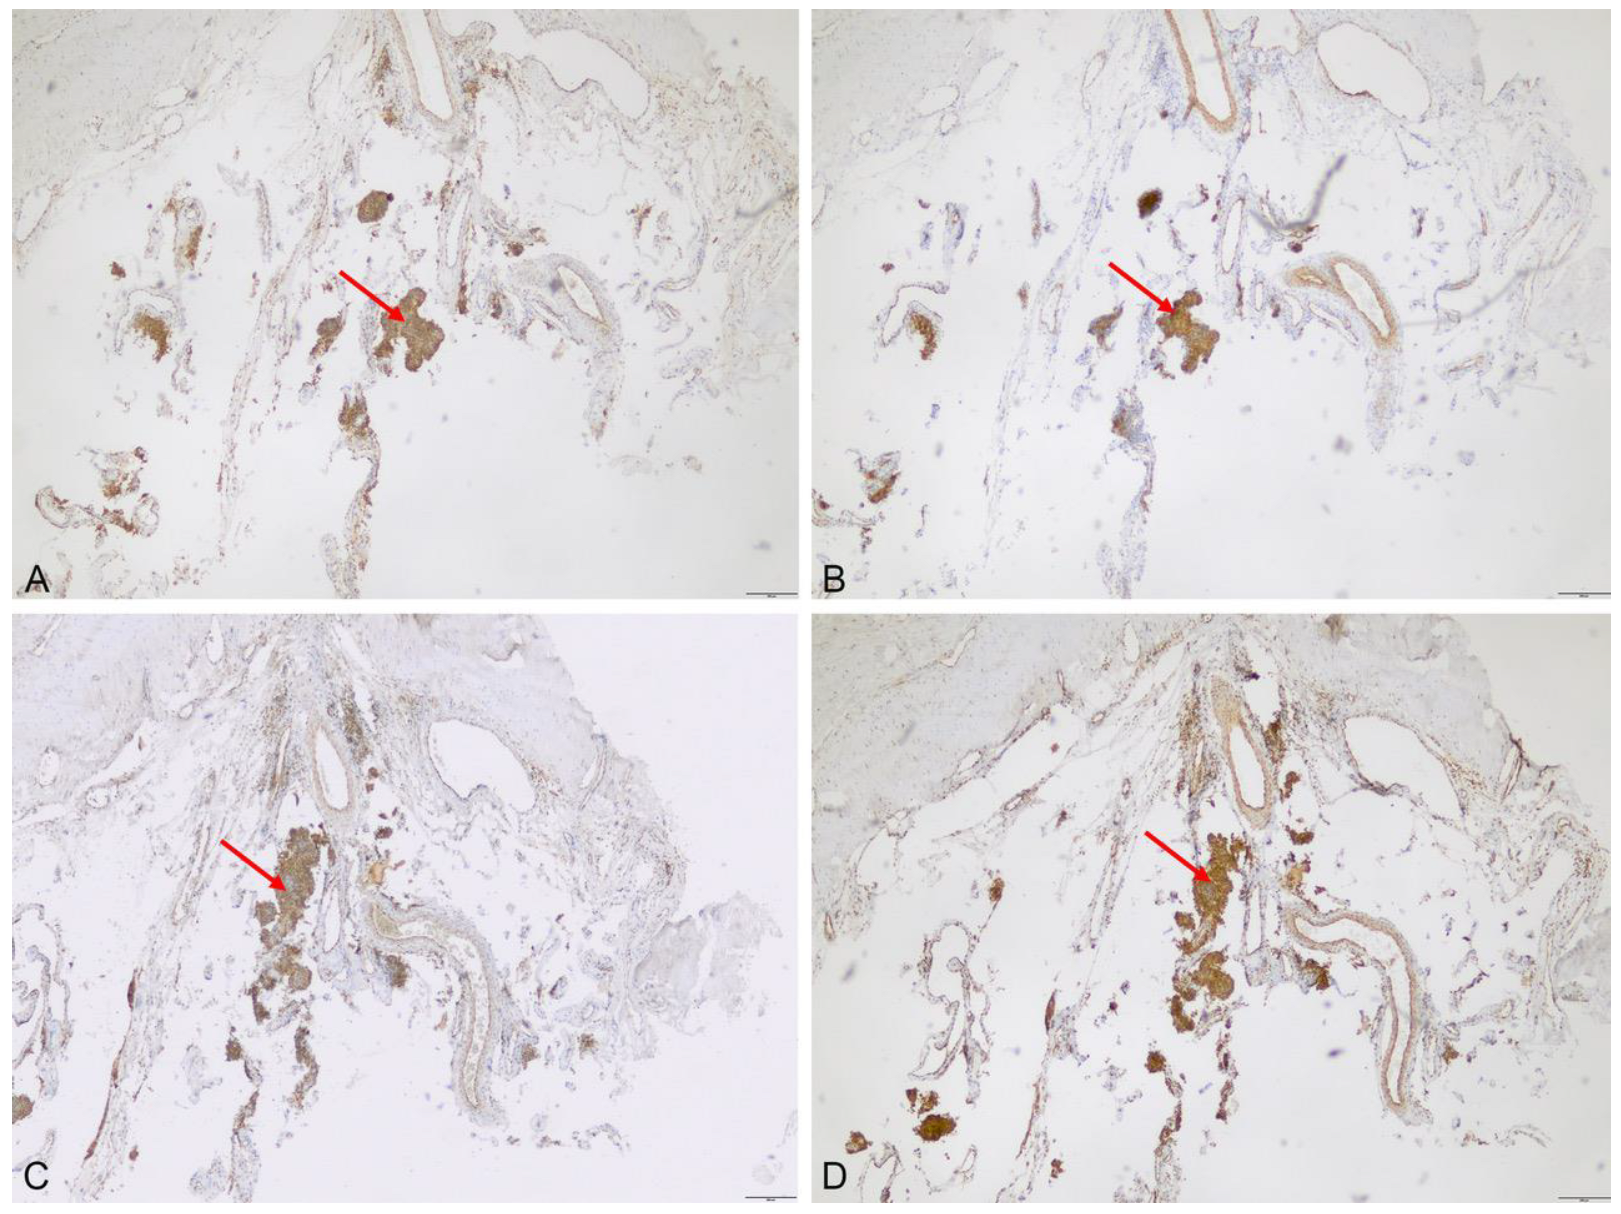

3.2.1. Immunhistochemistry